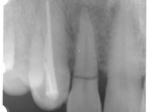

術前術前骨の高さが不足している場合、通常のインプラントでは処置が不可能なものが多い。特殊なショートインプラントを用いて可能になる例。 術前 術前CT像術前CT像術前CT像、下歯槽神経が下あごの中央部を走行しているため利用できる骨の高さが少ない。 埋入予定計画埋入予定計画埋入予定計画 術後レントゲン術後レントゲン、ひだりは少し神経をおそれすぎてやや埋入深度が不足、しかしこれでもしっかりと骨と固着した。